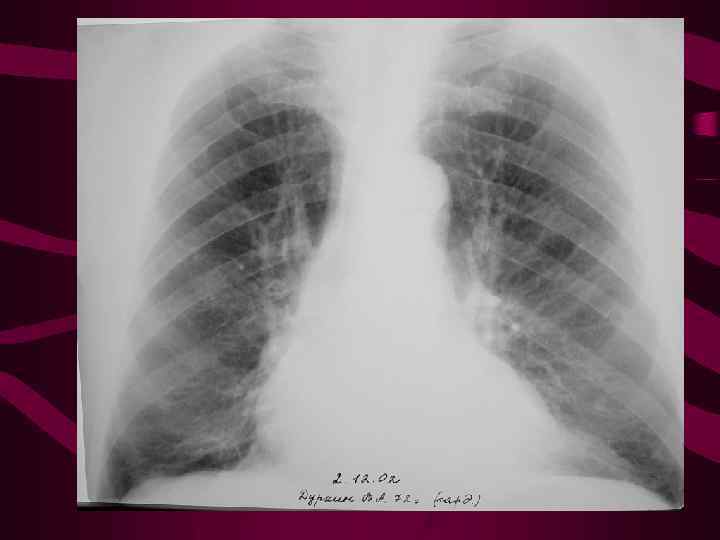

1 -верхнедолевой Усилен легочный рисунок в венозный застой верхних долях, укрупнен колибр (инверсия верхнедолевых вен. легочного Корни легких обычной величины, кровотока) но может отмечаться его незначительное расширение и увеличение колибра ортогональных теней сосудов в центральных отделах корня. Среднее давление в левом предсердии от 10 до 15 мм рт. ст.

1 -верхнедолевой Усилен легочный рисунок в венозный застой верхних долях, укрупнен колибр (инверсия верхнедолевых вен. легочного Корни легких обычной величины, кровотока) но может отмечаться его незначительное расширение и увеличение колибра ортогональных теней сосудов в центральных отделах корня. Среднее давление в левом предсердии от 10 до 15 мм рт. ст.

2 - диффузный венозный застой Среднее давление в левом предсердии от 15 до 25 мм рт. ст. Усилен венозный легочный рисунок во всех отделах легких до перифирии. Увеличено количество сосудистых теней на единицу площади легочного поля. Корни легких расширены структура их не диффе ренцируется. Отмечается нерезкость контуров корня и сосудов.

2 - диффузный венозный застой Среднее давление в левом предсердии от 15 до 25 мм рт. ст. Усилен венозный легочный рисунок во всех отделах легких до перифирии. Увеличено количество сосудистых теней на единицу площади легочного поля. Корни легких расширены структура их не диффе ренцируется. Отмечается нерезкость контуров корня и сосудов.